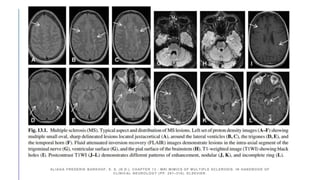

ALIAGA FREDERIK BARKHOF, E. S. (N.D.). CHAPTER 13 - MRI MIMICS OF MULTIPLE SCLEROSIS. IN HANDBOOK OF